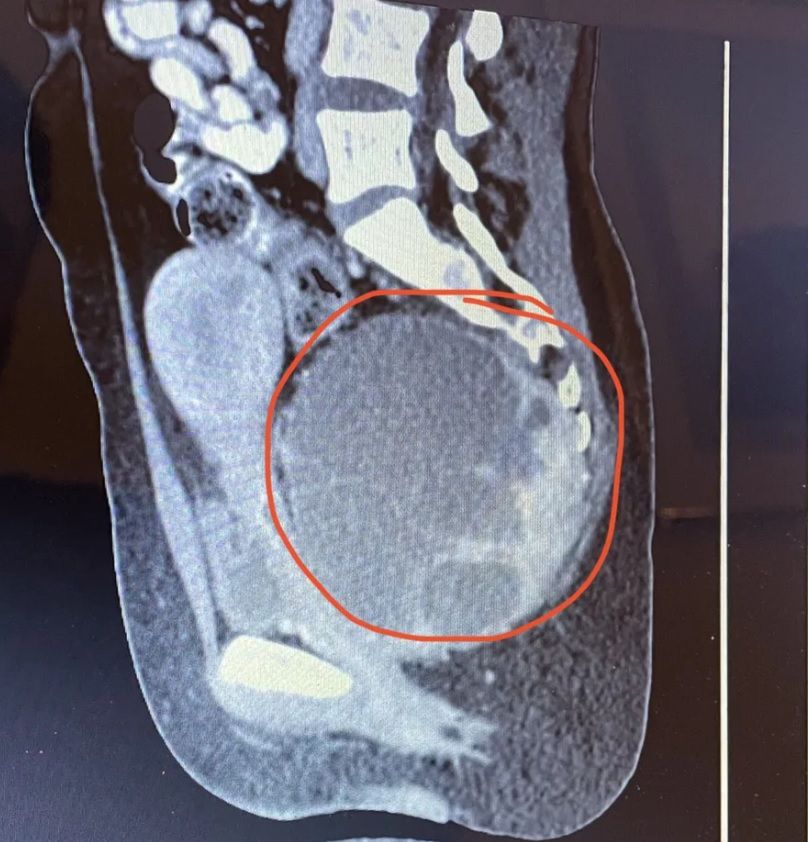

Badanie ujawniło przerażającą prawdę. U kobiety zdiagnozowano rzadkiego (14 cm) guza olbrzymiokomórkowego u podstawy kręgosłupa.

- Najpierw poszłam na USG, a następnego dnia na tomografię komputerową i wtedy znaleźli guza - wspomina Ellie Chandler.

- Stamtąd zostałam skierowana do szpitala na około tydzień, gdzie wykonano biopsję. Lekarze powiedzieli, że to guz olbrzymiokomórkowy, który nie jest rakowy. Ze względu na to, gdzie się znajduje, czyli w kości ogonowej i dolnej części kręgosłupa, może stać się masywny, zanim jeszcze pojawią się silne objawy - wyjaśnia 25-latka.

- Lekarze raczej nie myślą, że to może być guz, ponieważ jesteś młody i zdrowy. Wszystko to przyczyniło się do tego, że guz stał się tak masywny. W momencie, gdy go znaleźli był wielkości główki dziecka - podkreśla 25-latka.